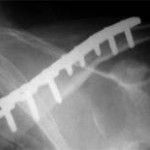

Clavicle fractures: Are we overtreating?

Clavicle fractures: Are we overtreating? Hitesh Gopalan U Editor, www.orthopaedicprinciples.com In the Blog @ Orthopaedic Principles It has been well described that we need to fix clavicle fractures that are open, those that are at risk for impending skin compromise, associated neurovascular injuries, floating shoulder. But the entire scenario changed when the COTS (Canadian […]